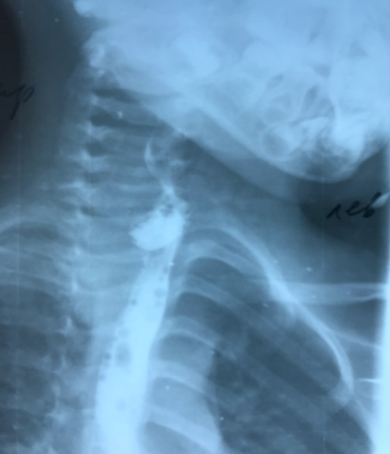

The postoperative period was uneventful, therapy included the use of a wide range of antibacterial therapy, regenerative drugs, against the background of which the inflammatory phenomena were arrested. A narrowing of the esophagus up to 15 mm was noted on the control contrast esophagography performed on the 15th day after the operation (Fig. 2). | Figure 2. Contrast esophagography after surgery: there is a narrowing of the esophagus lumen and no contrast extravasation |